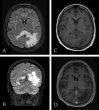

Background: Progressive multifocal leukoencephalopathy is a rare central nervous system disease, resulting from reactivation of latent John Cunningham virus. Monoclonal antibodies have recently become a relevant risk factor for developing progressive multifocal leukoencephalopathy. We report the case of a 62-year-old Caucasian man who was admitted to our department in June 2020 because of right homonymous hemianopia. Magnetic resonance imaging findings were first interpreted as an intracranial relapsed lymphoma, so brain biopsy was performed, but no neoplastic cell was found. Histological sample only showed a large number of macrophages. The patient came back to our attention because of the worsening of neurological symptoms. A second magnetic resonance imaging showed widespread lesions suggestive of a demyelinating process. John Cunningham virus DNA was detected by polymerase chain reaction assay of the cerebrospinal fluid (over 9 million units/μL). The patient was treated supportively, but the outcome was poor.